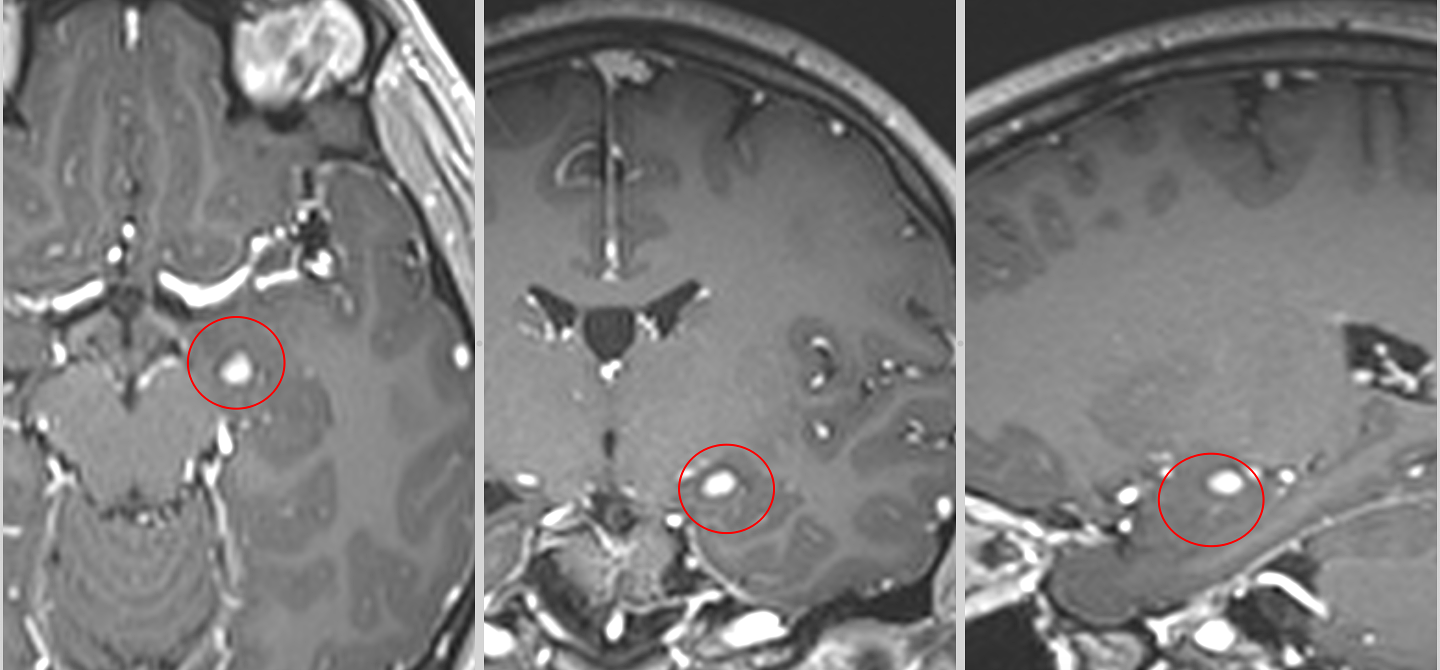

Operația s-a desfășurat în condiții foarte bune, fără incidente, iar tumora a putut fi rezecată complet, fără afectarea structurilor din jur.

Primele imagini RMN realizate imediat după intervenție au confirmat absența complicațiilor. Câteva săptămâni mai târziu, un nou control imagistic a arătat clar rezultatul: tumora fusese îndepărtată în totalitate.